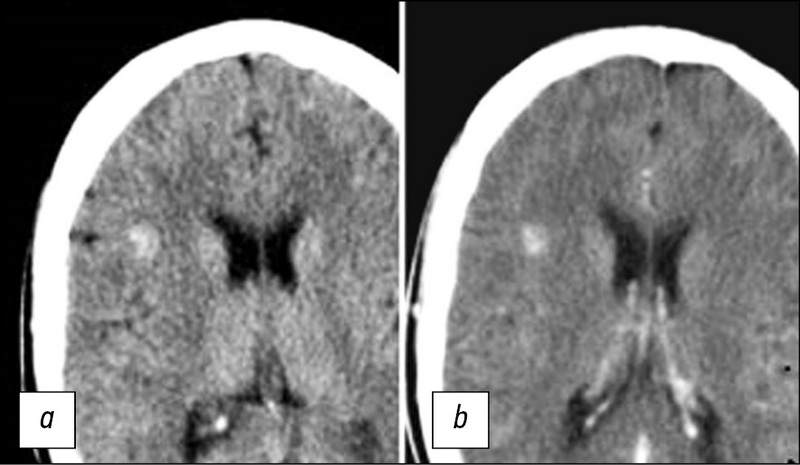

Radiation diagnostics of cerebral cavernous malformations

Cerebral cavernous malformations are a fairly common vascular pathology at the moment, with the number of detected cases increasing dramatically in recent years. This is because modern neuroimaging methods such as computed tomography (CT) and magnetic resonance imaging (MRI) have been introduced into clinical practice and are widely available. Prior to the advent of CT and MRI technologies, it was extremely difficult to diagnose this pathology, and the diagnosis was usually made intraoperatively or based on autopsy data. Further, the literature review is devoted to the radiological diagnosis of cerebral cavernous malformations (CM). The role of neuroimaging methods in the diagnosis of cavernous malformations, as well as the use of MRI for CM visualization, was analyzed. The advantages of MRI over other neuroimaging methods for this pathology have been demonstrated. Pulse sequences of MRI and signaling characteristics of various foci were characterized, depending on the morphological substrate. The significance of the susceptibility-weighted imaging sequence was also evaluated for the detection of multifocal lesions in cases of familial CM. The study of the main pulse sequences of MRI for visualization of CM will improve the protocol algorithm for the timely diagnosis of this pathology and the selection of therapeutic approach.